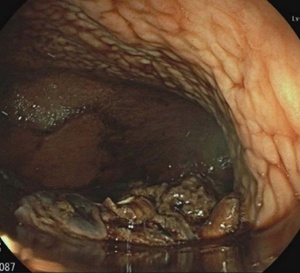

Treatment with a prophylactic dose of apixaban, an oral inhibitor of factor Xa, was prescribed. The thoraco-abdominal computed tomography (CT) scan showed, in addition to the liver lesions, the presence of hepatic hilar, retroperitoneal and mediastinal lymphadenopathies, mild splenomegaly and minimal pelvic ascites (Figure 2). After a multidisciplinary discussion, the tumor was considered unresectable.